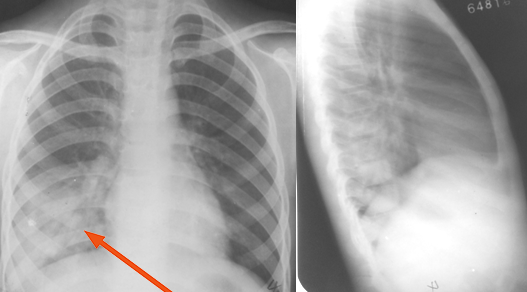

右肺下叶后基底段大叶性炎症

图片

胸部正侧位片:右肺下叶见片状致密影,右侧膈面及邻近胸廓边缘模糊(箭头所示),心缘清楚